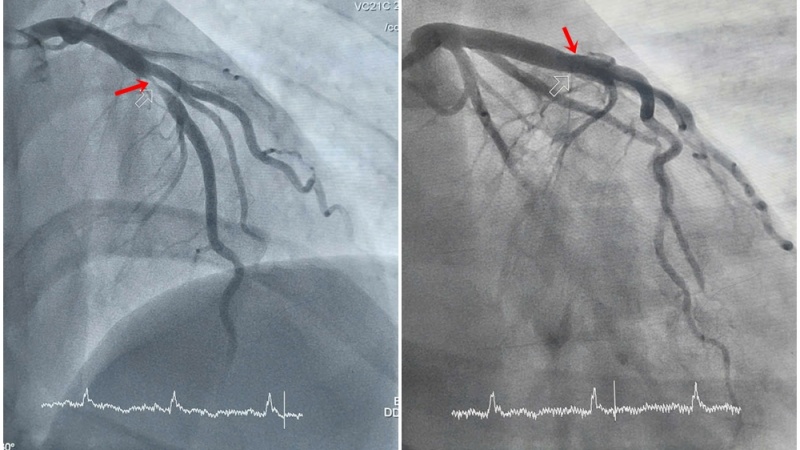

Hình ảnh hẹp tắc động mạch liên thất trước của bệnh nhân được can thiệp tái thông - Ảnh: BVCC.

Qua thăm khám lâm sàng kết hợp các xét nghiệm cận lâm sàng, các bác sĩ chẩn đoán anh bị nhồi máu cơ tim cấp trước vách - một thể nhồi máu cơ tim nguy hiểm, có nguy cơ cao gây rối loạn nhịp tim, sốc tim, thậm chí ngừng tim và tử vong nếu không được xử trí kịp thời. Ngay sau đó, bệnh nhân được chuyển khẩn cấp đến phòng can thiệp tim mạch để chụp mạch vành.

Ê-kíp Khoa Phẫu thuật và Can thiệp Tim mạch đã nhanh chóng tiến hành đặt stent tái thông dòng máu nuôi tim cho bệnh nhân. Ca can thiệp diễn ra thuận lợi, giúp người bệnh vượt qua cơn nguy kịch. Tình trạng của bệnh nhân tiến triển tốt, không còn đau tức ngực, các chỉ số tim mạch dần ổn định và hồi phục nhanh.